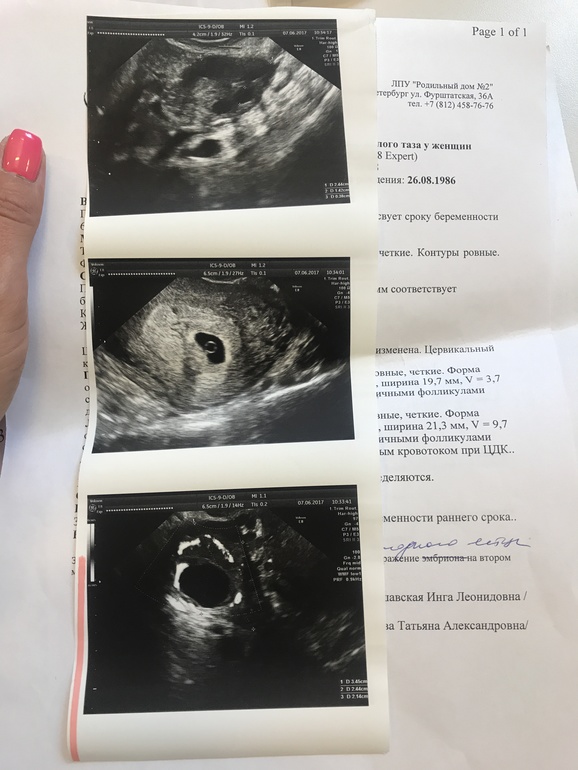

На Узи мне показали наше зернышко, срок 5-6 недель

, эмбриончик уже виден, сказала прийти через 7-10 дней чтобы посмотреть сердцебиение , пока еще рано !

А так все красиво и хорошо , угроз нет ! УФФФФФФФФФ счастье